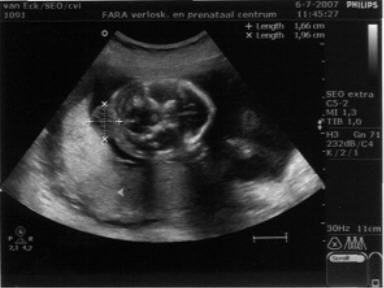

De eerste maanden verliepen zoals gewend. Mama was veel moe en groeide gestaag. Vol verwachting, maar ook wel zenuwachting, gingen we naar het echobureau voor een 20-weken-echo. Daar bleek al snel dat er iets niet goed was met ons kindje. We zagen een bult op het hoofdje, achter in de nek. De echoscopist kon ons niet verder helpen en verwees ons door naar een gyneacoloog.

Ontdaan en gespannen vertrokken we. Eenmaal thuis doken we achter internet. Wat was er aan de hand met ons kindje? We vonden medische informatie: het heette een encephalocele (ook wel geschreven als encefalocele), er worden in Nederland slechts een paar kinderen per jaar mee geboren en in de meeste gevallen is het een onderdeel van een syndroom, waardoor de kindjes niet levensvatbaar zijn. Ook lazen we verhalen van enkele ouders. In alle gevallen had hun kindje slechts kort geleefd. Wat stond ons te wachten?

De dag erna belde de gynaecoloog. De prenataal neuroloog uit Nijmegen schetste toch een heel ander beeld. Al snel konden we bij hem terecht. Op basis van de grootte en de plaats van de cele (uitstulping) gaf hij ons goede hoop: hij kende kinderen met soortgelijk beeld die gewoon op een gewone basisschool zaten. Wat een verschil met het vorige gesprek! Dit was meer dan het beste scenario tot dan toe!